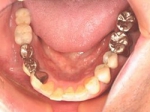

両側5歯症例

両側5歯症例両側5歯症例両側5歯症例 主訴-義歯のバネが壊れて手前の歯が痛んできた。 術前(旧義歯装着、鏡像) 術前(下顎粘膜面、鏡像)術前(下顎粘膜面、鏡像)術前(下顎粘膜面、鏡像) 術前レントゲン術前レントゲン術前レントゲン 術前口腔内(正面観)術前口腔内(正面観)術前口腔内(正面観)

術後(鏡像)術後(鏡像)術後(鏡像) 術後口腔内(正面観)術後口腔内(正面観)術後口腔内(正面観)もう入れ歯は要らなくなりました。 術後レントゲン術後レントゲン術後レントゲン